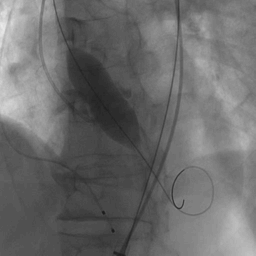

瓣膜释放完毕

患者即刻跨瓣压差显著下降,再行主动脉造影提示瓣膜置入位置良好、形态完整,未见瓣周漏,未出现相关并发症,取得了良好的手术结果。